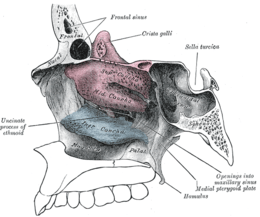

Orbital bones Lateral wall of nasal cavity, showing ethmoid bone in position.

Lateral wall of nasal cavity, showing ethmoid bone in position. Articulation of nasal and lacrimal bones with maxilla.

Sagittal section of skull. Roof, floor, and lateral wall of left nasal cavity.

Roof, floor, and lateral wall of left nasal cavity. Nasal bone